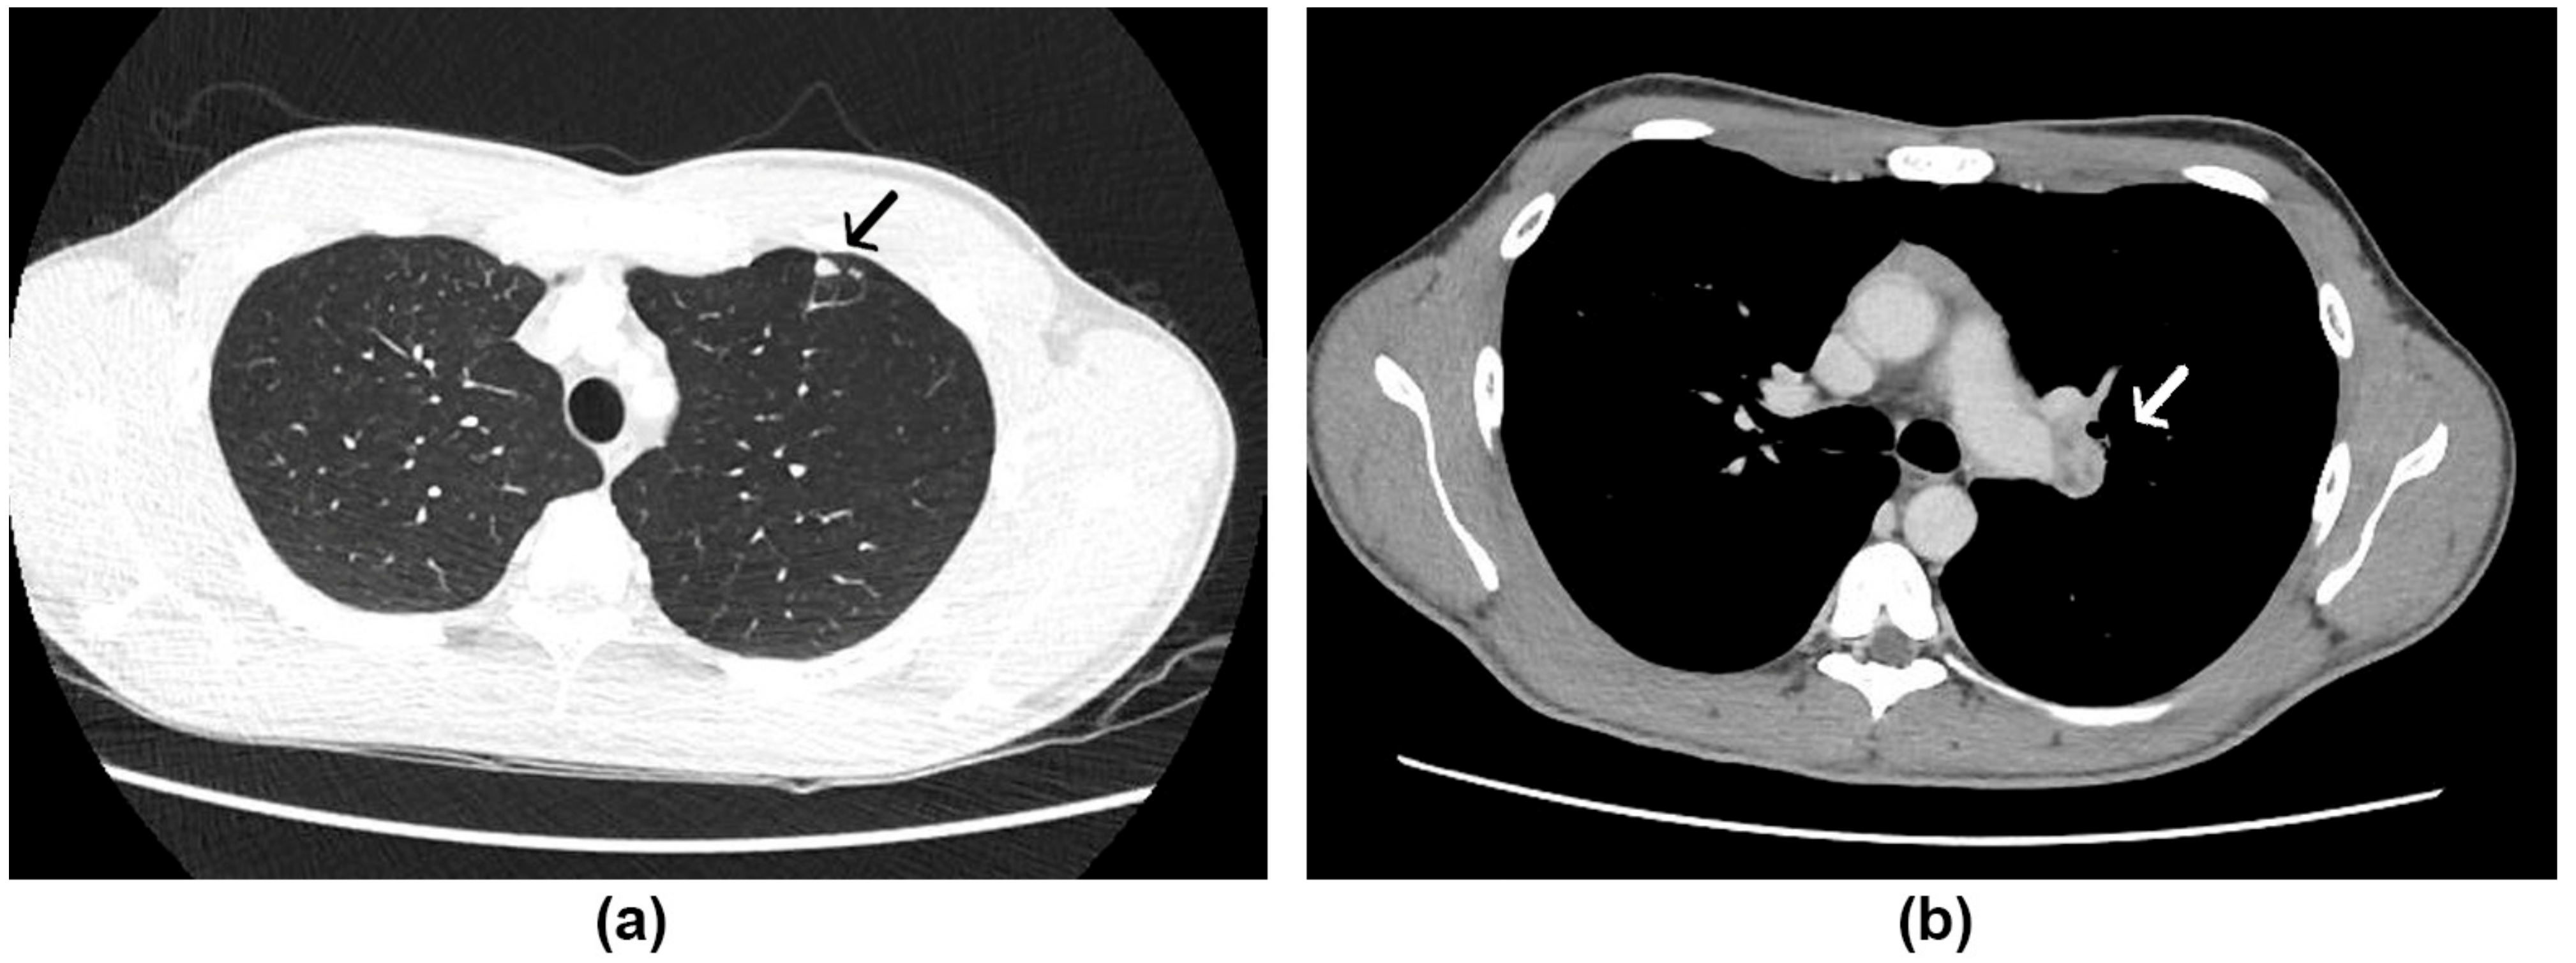

A 20-year-old male patient was admitted to the Evandro Chagas National Institute of Infectious Diseases (INI/Fiocruz), reporting high fever (39 °C) in the 1st week of February 2021. He had been followed by a pulmonologist due to a persistent dry cough after presenting a mild case of COVID-19 (confirmed through a positive real-time reverse-transcription PCR [RT-PCR] of a nasopharyngeal swab) 4 months before. The patient reported a great dust exposure while playing soccer on a ground field with bird excreta 5 weeks before the fever presented. The initial investigation included a chest tomography, which revealed small nodular opacities without calcifications, measuring up to 0.8 cm, on the periphery of the anterior segment of the upper left lobe, associated with some confluent vessels, as well as left pulmonary hilum enlargement, and small mediastinal lymph nodes (Figure 1).

Figure 1. Chest tomography of case 1: (a) Nodular opacities on the periphery of the anterior segment of the upper left lobe (black arrow), (b) mediastinal lymph nodes (white arrow).